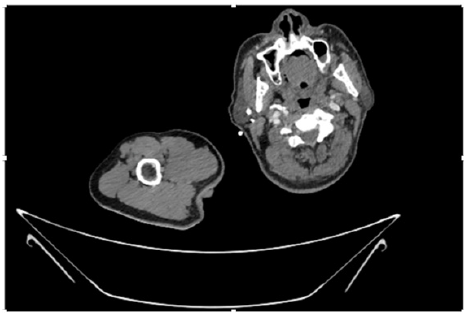

Figure 4: CT Angiogram at neck showing normal brachio-cephalic trunk, common carotid artery, and narrow right subclavian artery.

Figure 5: CT Angiogram at neck showing normal brachio-cephalic trunk, common carotid artery, and narrow right subclavian artery.

Figure 6: CT Angiogram at neck showing brachio-cephalic trunk, common carotid artery and narrow right subclavian artery.

Figure 7: CT Angiogram at neck showing brachio-cephalic trunk, common carotid artery and narrow right subclavian artery.

Figure 10: CT Angiogram at upper arm showing totally occluded right axillary artery; normal internal carotid artery and external carotid artery.